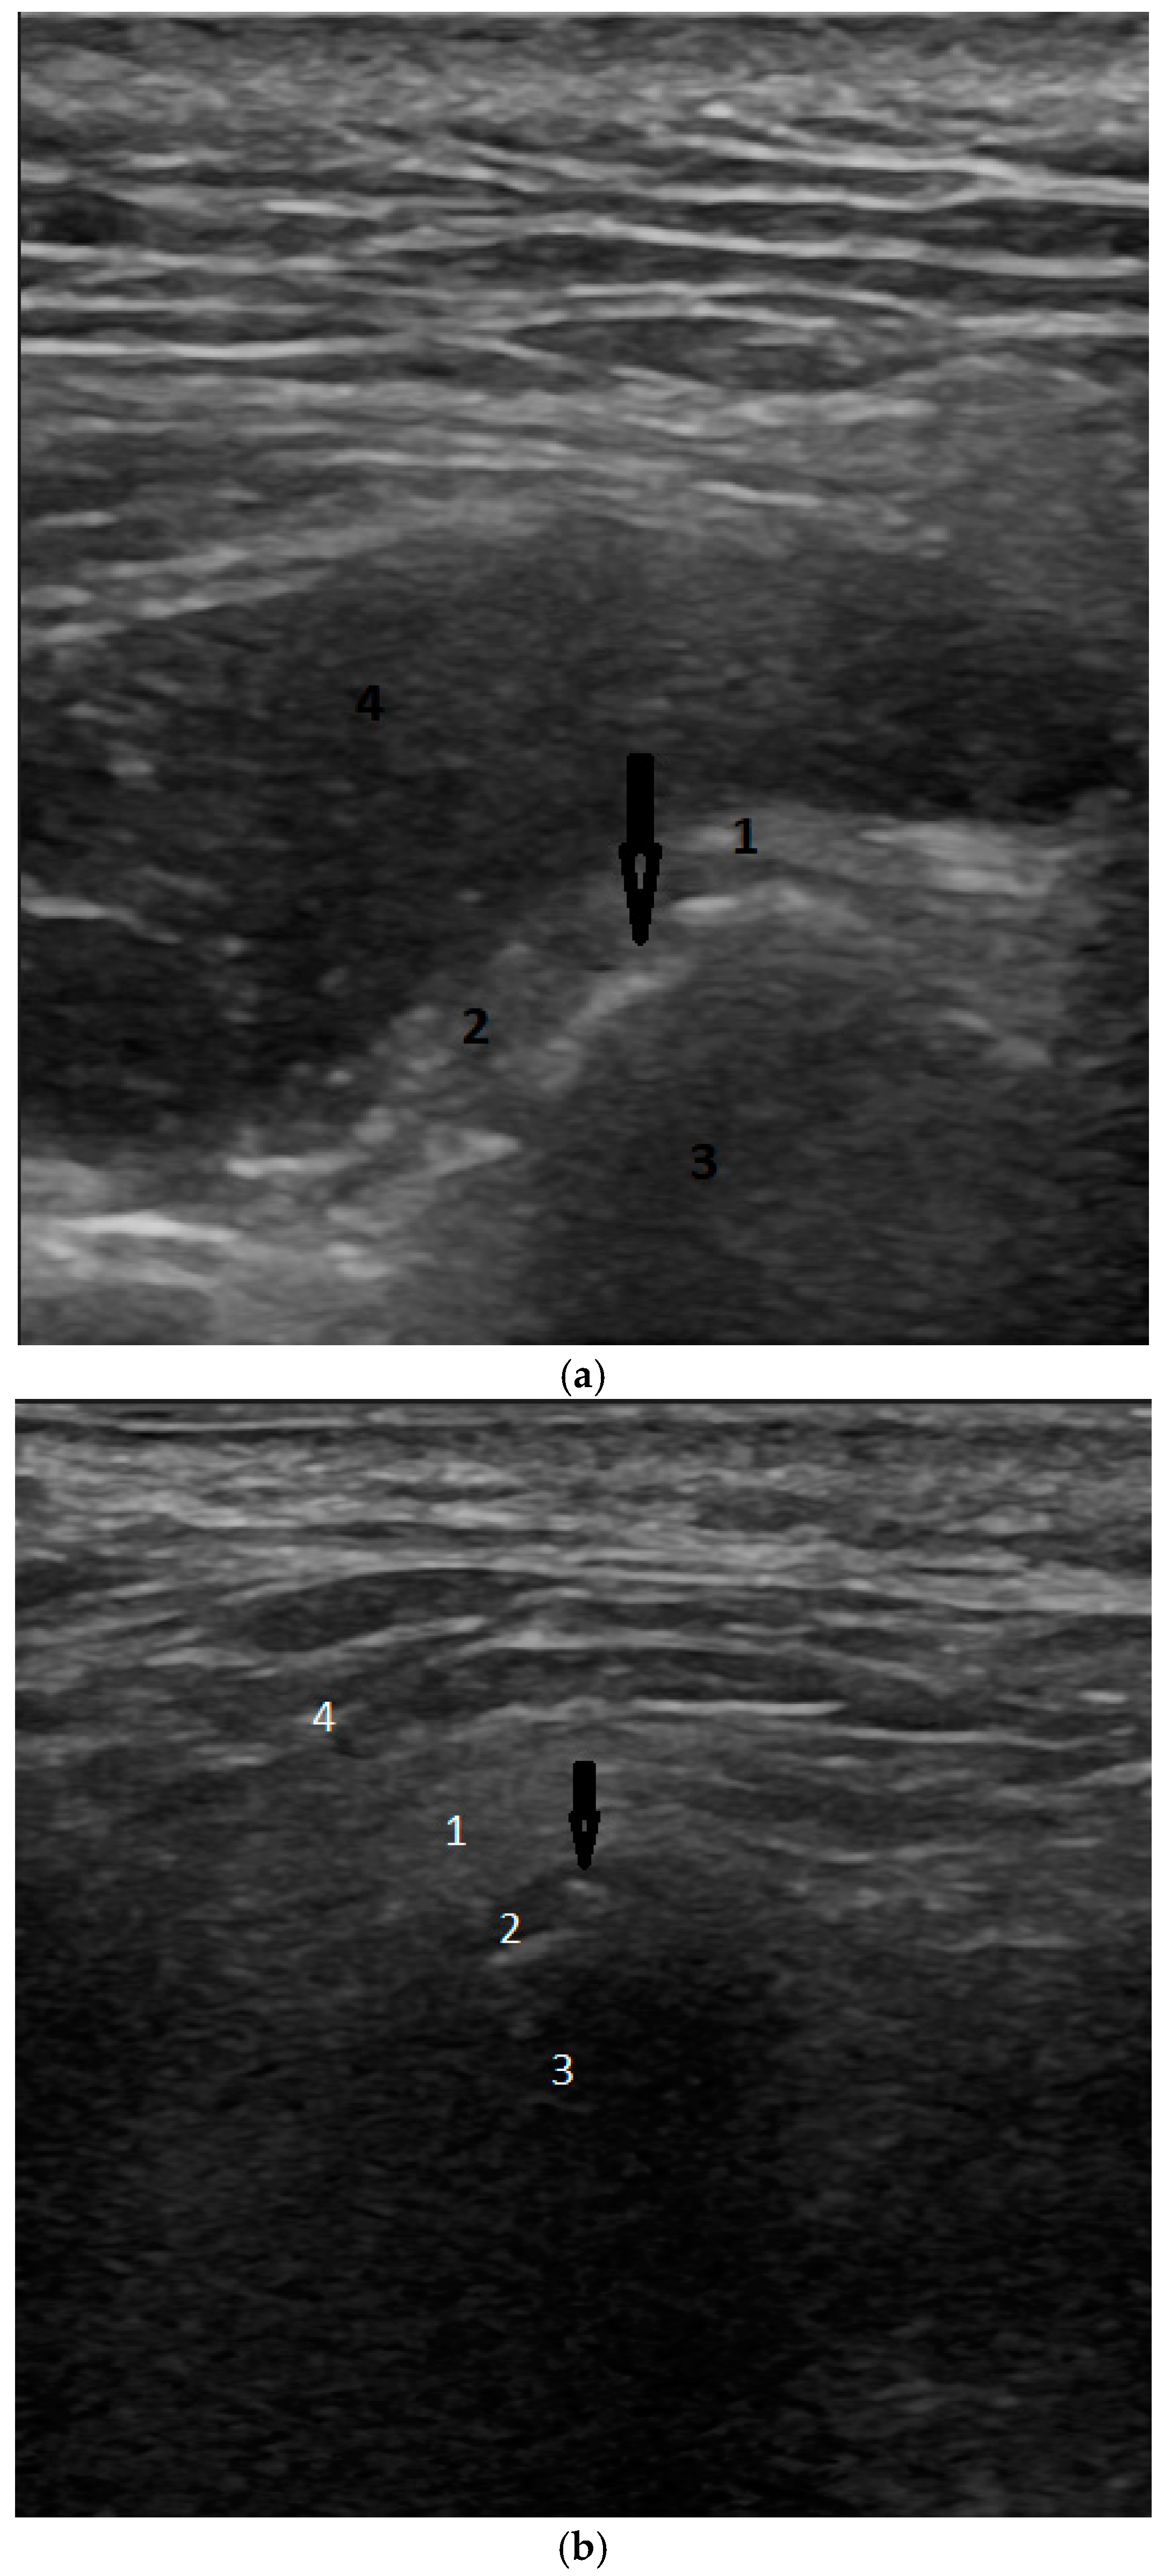

- Zaman, M.U.; Alam, M.K.; Alqhtani, N.R.; Alqahtani, M.; Alsaadi, M.J.; Ronsivalle, V.; Cicciù, M.; Minervini, G. Effectiveness of ultrasonography in the diagnosis of temporomandibular joint disorders: A systematic review and meta-analysis. J. Oral Rehabil. 2024. ahead of printing. [Google Scholar] [CrossRef]

- Manfredini, D.; Guarda-Nardini, L. Ultrasonography of the temporomandibular joint: A literature review. Int. J. Oral Maxillofac. Surg. 2009, 38, 1229–1236. [Google Scholar] [CrossRef]

- Klatkiewicz, T.; Gawriołek, K.; Pobudek Radzikowska, M.; Czajka-Jakubowska, A. Ultrasonography in the Diagnosis of Temporomandibular Disorders: A Meta-Analysis. Med. Sci. Monit. 2018, 24, 812–817. [Google Scholar] [CrossRef]